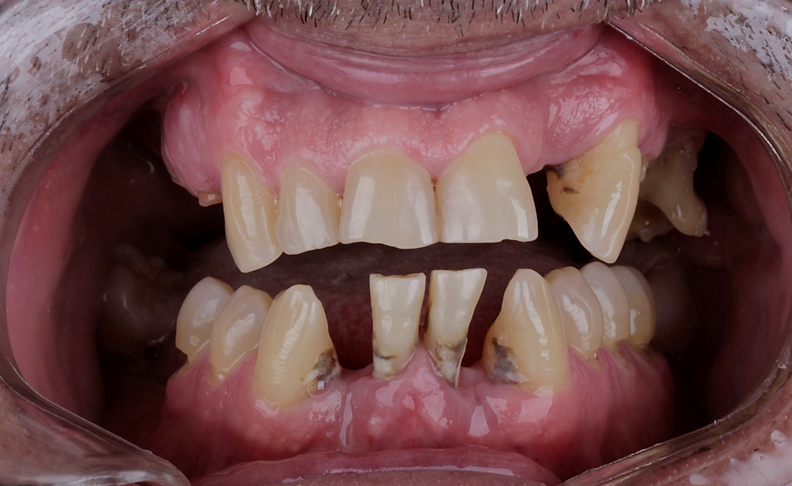

Um paciente procurou tratamento protético reabilitador com queixa dos dentes 31 e 41 que estavam abalados. Ao exame clínico e radiográfico, notou-se mobilidade dos dentes, doença periodontal ativa e perda óssea.

Avaliamos o espaço mésio-distal entre os dentes 33 e 43 e constatamos a ausência de distância para a colocação de implantes individualizados. Assim sendo, optamos pela instalação de dois implantes Veloce CM de diâmetro 3.3 e pilares do tipo micro-cônico para a solução clínica.